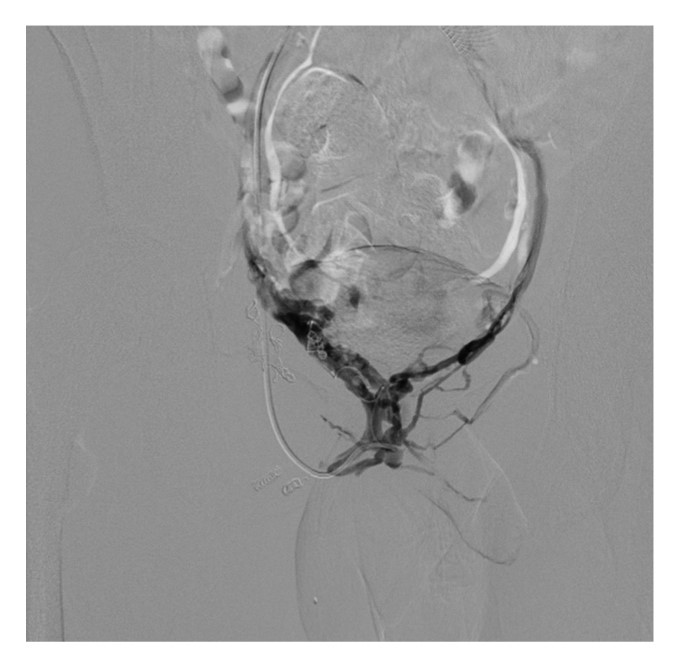

На следующем этапе в область парапростатического сплетения проведен и установлен микрокатетер «Progreat» 2,4F 150 см на смонтированном 0,018” микропроводнике. Проводник извлечен, выполнена флебография целевой области для уточнения анатомии (рис. 9).

Рис. 9. Флебограмма пациента К. (в режиме DSA) характерной «бабочки» парапростатического венозного сплетения у основания мочевого пузыря.